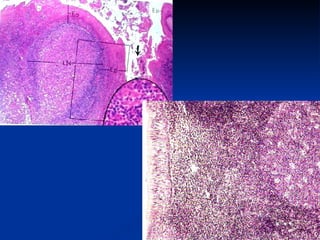

Linfonodos Cortical (córtex) – periférica  Cortical superficial – abaixo da cápsula Seios subcapsulares e peritrabeculares Folículos (nódulos) linfáticos – condensação esférica de linfócitos Linfócitos B Cortical profunda (paracortical) Linfócitos T Ausência de folículos linfáticos  Medular – central  Cordões medulares  – linfócitos B, plasmócitos, macrófagos e células reticulares Seios medulares

Linfonodos Cortical (córtex)– periférica Cortical superficial – abaixo da cápsula Seios subcapsulares e peritrabeculares Folículos (nódulos) linfáticos – condensação esférica de linfócitos Linfócitos B Cortical profunda (paracortical) Linfócitos T Ausência de folículos linfáticos Medular – central Cordões medulares – linfócitos B, plasmócitos, macrófagos e células reticulares Seios medulares

Regiões do linfonodo: córtex, paracórtex e medula

Regiões do linfonodo:córtex, paracórtex e medula

Linfonodo Nódulos linfóides primários   Agregados esféricos de linfócitos B (células B virgens e células B de memória) no córtex Nódulos linfóides secundários  Formados somente durante estimulo antigênico  Centro germinativo  Centro do nódulo linfático secundário corado mais claro – local de origem da célula B de memória e do plasmócito Coroa (manto)  Região periférica dos nódulos secundários – acúmulo de pequenos linfócitos migrados do seu local de origem (interior dos nódulos secundários)

Linfonodo Nódulos linfóidesprimários Agregados esféricos de linfócitos B (células B virgens e células B de memória) no córtex Nódulos linfóides secundários Formados somente durante estimulo antigênico Centro germinativo Centro do nódulo linfático secundário corado mais claro – local de origem da célula B de memória e do plasmócito Coroa (manto) Região periférica dos nódulos secundários – acúmulo de pequenos linfócitos migrados do seu local de origem (interior dos nódulos secundários)